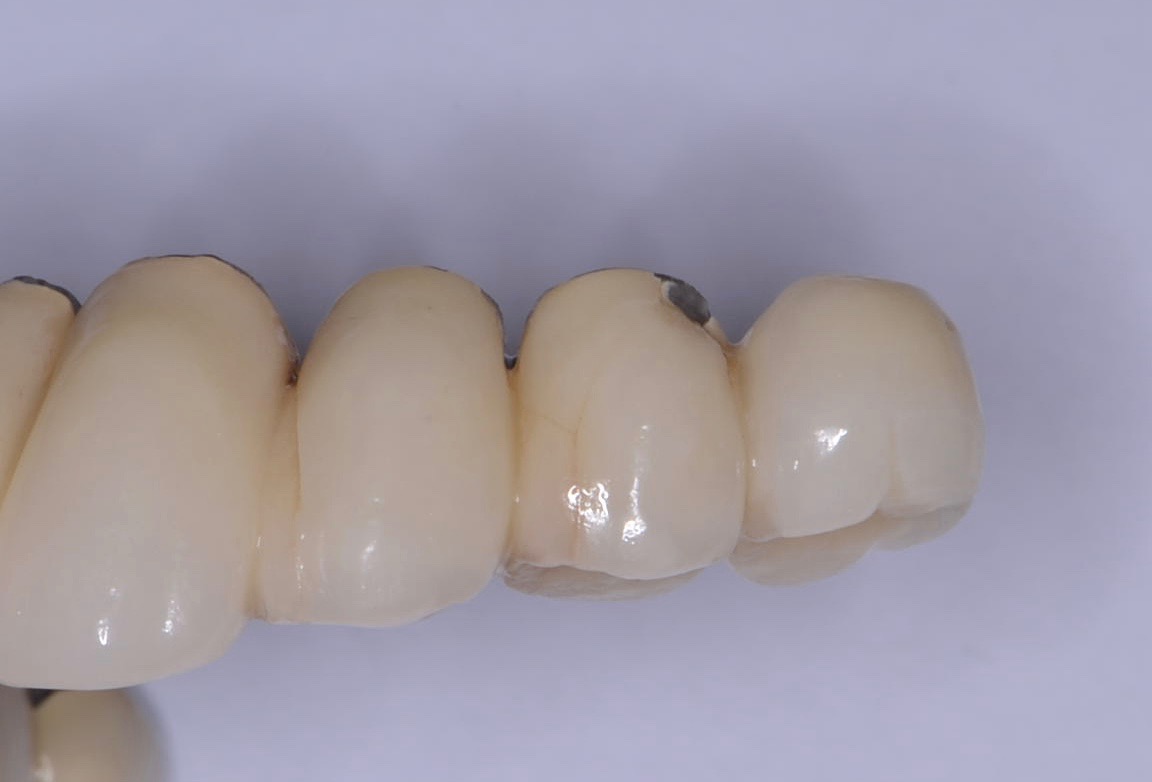

Fracture/Chipping of the Veneering Material

With 5-year complication rates from 3.2% to 25.5%,1 chipping of the veneering material (Figure 1) is the most common technical complication addressed in the literature.1,2 This can be minimized by designing the prosthesis before the final fabrication to ensure optimal framework design and thickness of the veneering material. Following basic occlusal principles in implant prosthodontics is essential. These include reduced cuspal inclination, narrow occlusal table, correction of load direction, reduced nonaxial loading, reduced length of the cantilever, and lighter occlusal contacts on implants.5 Restorations such as monolithic zirconia (Figure 2) and lithium disilicate are also being used to minimize chipping. However, long-term follow-up information on these restorations is limited.

Fig 1. Chipping of veneering porcelain of porcelain-fused-to-gold full-arch fixed dental prosthesis.

Figure 1